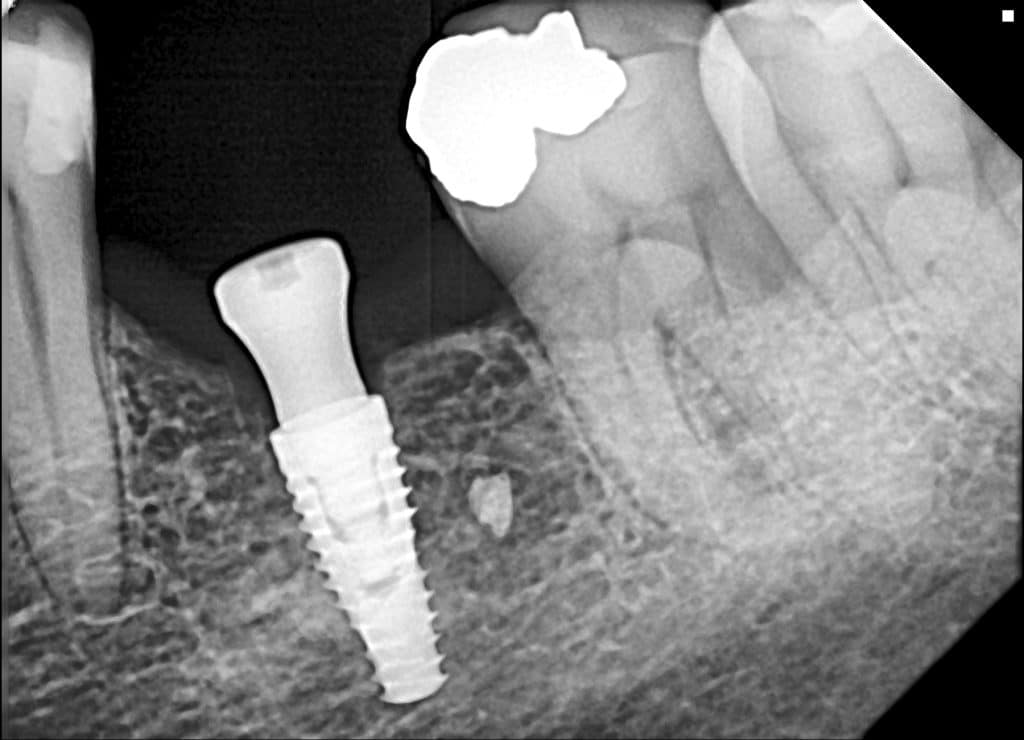

here a guided surgery case where a lower molar was replaces by an implant ,flapless ,thanks to a good digital planification and a realisation of a surgical guide